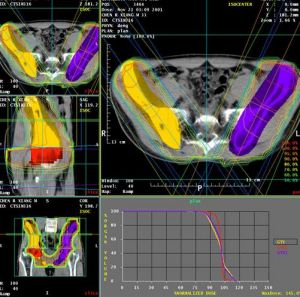

一、放射治療

HD的放射治療已取得顯著成就。較為有效,但最好套用直線加速器。用高能射線大面積照射HDⅠA至ⅡB的方法有擴大及全身淋巴結照射兩種。擴大照射除被累計的淋巴結及腫瘤組織外,尚須包括附近可能侵及的淋巴結區,例如病變在隔上採用斗篷式。隔下倒“Y”字式。斗篷式照射部位包括兩側從乳突端之鎖骨上下,腋下、肺門、縱隔以至隔的淋巴結;要保護肱骨頭、喉部及肺部免收照射。倒“Y”式照射包括從膈下淋巴結至腹主動脈旁、盆腔及腹股溝的淋巴結,同時照射脾區。劑量為30~40Gy,3~4周為一療程。全身淋巴結照射即膈上為斗篷式並加照膈下倒“Y”字式。 HNL對放療也敏感但復發率高。由於其蔓延途徑不是沿淋巴區,所以斗篷和倒“Y”字式大面積不規則照射野的重要性遠較HD為差。治療劑量要大於HD。目前僅低度惡性組臨床Ⅰ及Ⅱ期及中度惡性組病理分期Ⅰ期可單獨套用擴大野照射或單用累及野局部照射。放療後愛否再用化療,意見尚不統一。Ⅲ及Ⅳ期多採用華萊為主,必要時局部放療為姑息治療。二、化學治療